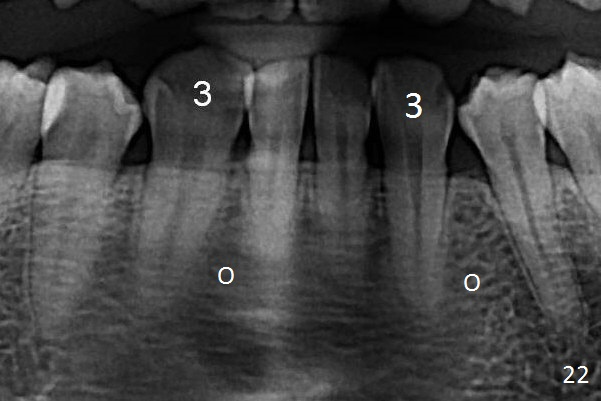

A 41-year-old woman requests orthodontic treatment because of the upper blocked out canines (Fig.6,8). Her facial and dental midlines coincide (Fig.1). Her profile is slightly convex (Fig.2,3) with increase in overjet (Fig.4). Orthodontic treatment includes extraction of U4s and placement of 2 mini-implants between U5 and 6 (Fig.5 o) when arch wires change to 18x25. Power arms (as high as possible) are placed between U2 and 3. U1-3s are retracted at the same time (en mass) because of absolute anchorage of the mini-implants. Retraction time will be reduced. Interproximal reduction (IPR) will be done especially at LR3 (macrodontia, Fig.5) if the lower arch turns out to be too large.

The rotation of the upper canines is not corrected much in the next 3.5 months (Fig.21, as compared to Fig.18). Distalization of the upper right canine is implemented by power chain, but this is not sufficient because of the anterior deep bite. Note the tension of 18 niti wire between LR 3 and 4 (^). Mini implants are going to be placed mesial or distal to L3s (Fig.22,23 circles) to intrude the lower anterior teeth with elastic or power chain (Fig.23 red line, 24 black area). The upper anteriors will have space to be distalized (Fig.24 arrow). If necessary, proximal reduction will be accomplished at LR3 (extra wide, Fig.25 black outline) for further overjet correction (arrows).